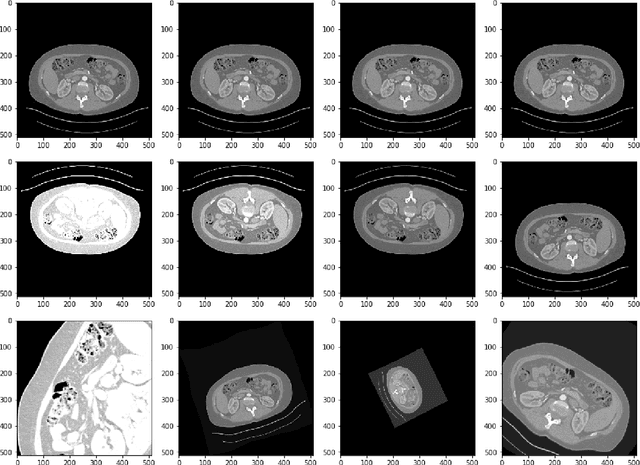

Abstract:Accurate segmentation of kidneys and kidney tumors is an essential step for radiomic analysis as well as developing advanced surgical planning techniques. In clinical analysis, the segmentation is currently performed by clinicians from the visual inspection images gathered through a computed tomography (CT) scan. This process is laborious and its success significantly depends on previous experience. Moreover, the uncertainty in the tumor location and heterogeneity of scans across patients increases the error rate. To tackle this issue, computer-aided segmentation based on deep learning techniques have become increasingly popular. We present a multi-scale supervised 3D U-Net, MSS U-Net, to automatically segment kidneys and kidney tumors from CT images. Our architecture combines deep supervision with exponential logarithmic loss to increase the 3D U-Net training efficiency. Furthermore, we introduce a connected-component based post processing method to enhance the performance of the overall process. This architecture shows superior performance compared to state-of-the-art works using data from KiTS19 public dataset, with the Dice coefficient of kidney and tumor up to 0.969 and 0.805 respectively. The segmentation techniques introduced in this paper have been tested in the KiTS19 challenge with its corresponding dataset.